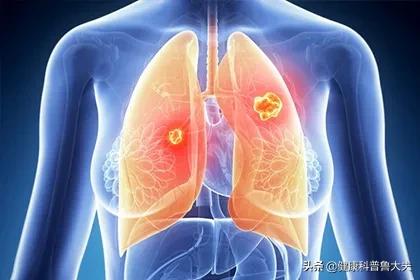

L'adénocarcinome pulmonaire le plus dangereux

L'adénocarcinome pulmonaire a désormais dépassé le cancer squameux du poumon en tant que type le plus courant de tumeur maligne du poumon, avec une prévalence chez les femmes et un nombre croissant de patients plus jeunes.

L'adénocarcinome pulmonaire est mûr pour une croissance rapide et des métastases partout. L'hyperplasie alvéolaire augmente en densité et mesure généralement moins de 5 mm, quelques-unes dépassant 10 mm.

Chez certains patients, les nodules continueront à évoluer vers un carcinome in situ, tandis que chez d'autres, les nodules n'évolueront plus et resteront tels quels. Lorsque le nodule progresse, il devient cancéreux, mais les cellules cancéreuses sont toutes confinées dans la cavité alvéolaire et ne s'agrègent pas. Le nodule est généralement plus grand que 5 mm et sa densité a légèrement augmenté.

Avec le développement ultérieur, les cellules tumorales se développent davantage et traversent la cavité alvéolaire, ce qui est appelé adénocarcinome micro-infiltrant. Le corps complet de l'adénocarcinome présente la structure complète de la tumeur, mais l'infiltration interstitielle et vasculaire est inférieure à 5 mm. À ce moment de la résection, le taux de survie est également proche de 100 %.

S'il se développe davantage et forme des structures folliculaires, papillaires ou micropapillaires de plus de 5 mm de diamètre, on parle d'adénocarcinome invasif ou d'adénocarcinome pulmonaire. C'est à ce moment-là qu'il devient dangereux !